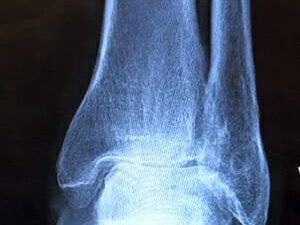

PJ delves into the complexities of rehab and recovery, pointing out how factors like age, gender, weight, range of motion, and scar tissue can impact the success of knee surgery. He introduces the X10 knee recovery system, a cloud-connected device designed to assist individuals in their recovery process by providing gentle yet relentless exercises to improve bending and straightening without causing pain, swelling, or scar tissue.